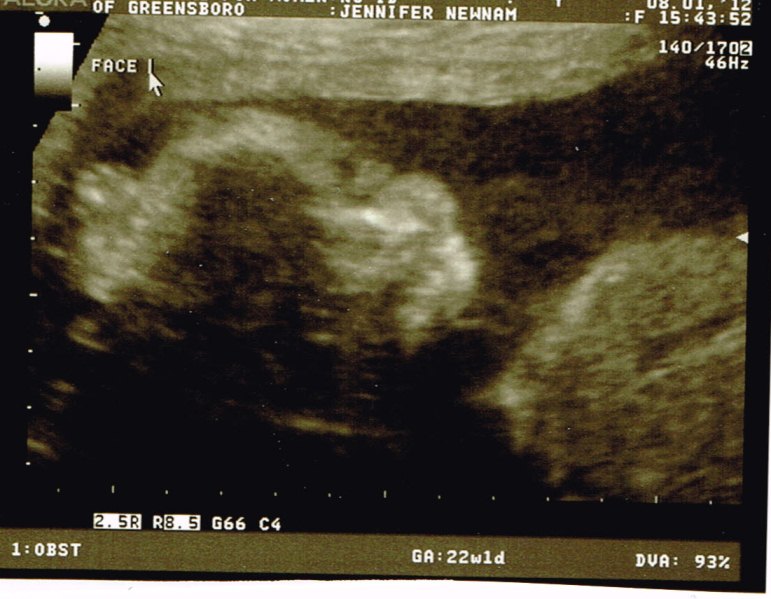

Here are a few new pictures of our baby boy.

Face shot!